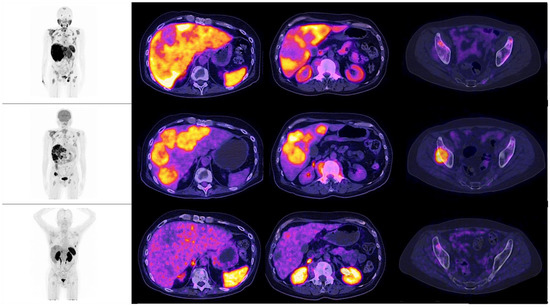

Figure 2. Patient number 4, a 54-year-old male, with an initial histopathological report of prostate adenocarcinoma, and a Gleason score of 9 (4 + 5). He was treated with surgical transurethral resection of the prostate + androgen deprivation therapy + chemotherapy. Site of second biopsy was post-surgical prostate bed, with a confirmatory report of neuroendocrine carcinoma (positive immunohistochemistry for chromogranin and synaptophysin). Time lapse to neuroendocrine differentiation was 15 months, with a PSA value of 137.3 ng/dL when NED was detected. In the illustrations, multiple hepatic lesions are appreciated, all of them with an increase of the glycolytic metabolism, with no evidence whatsoever, of expression of PSMA nor somatostatin receptors, by molecular imaging.

When observing the lesions and the percentage of uptake by a semi-quantitative assessment, which was determined by SUVmax for each radiopharmaceutical, it was found that the positive uptake of 18F–PSMA-1007 is greater at bone lesions, lymph node and seminal vesicles compared with the other radiotracers. Conspicuously, FDG was identified as the best radiotracer for the overall identification of lesions, with an outstanding detection of visceral metastases (see Figure 2 and Figure 3).